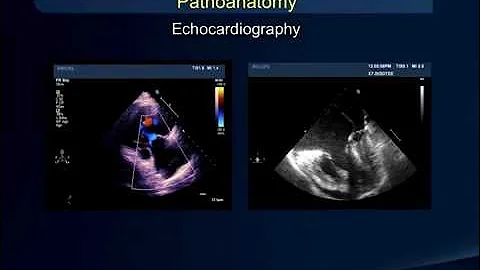

Jerome S. Zacks, MD, was the featured guest for Luncheon with the Experts on January 7, 2021. Dr. Zacks, a cardiologist, has ...